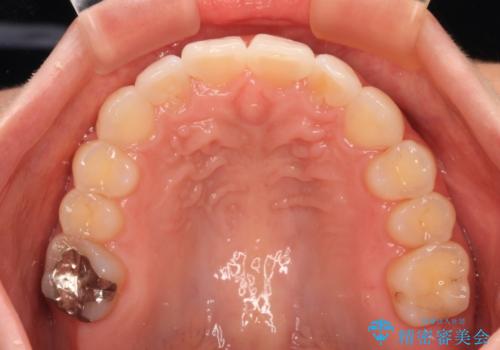

- 前歯のデコボコで前方に出ていることを気にして来院された患者様です。

上顎前歯が捻れて前方に飛び出しており、下顎前歯もそれに沿うようにデコボコとなっていました。

IPR(歯と歯の間を削る処置)によりスペースを獲得して上下顎前歯のデコボコを改善し、飛び出している前歯が引っ込むように設定し、インビザラインにて矯正治療を行うこととしました。